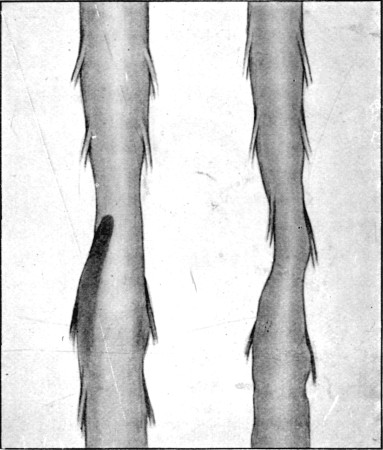

49. Explosive Exit and Entry Wounds of Legs159